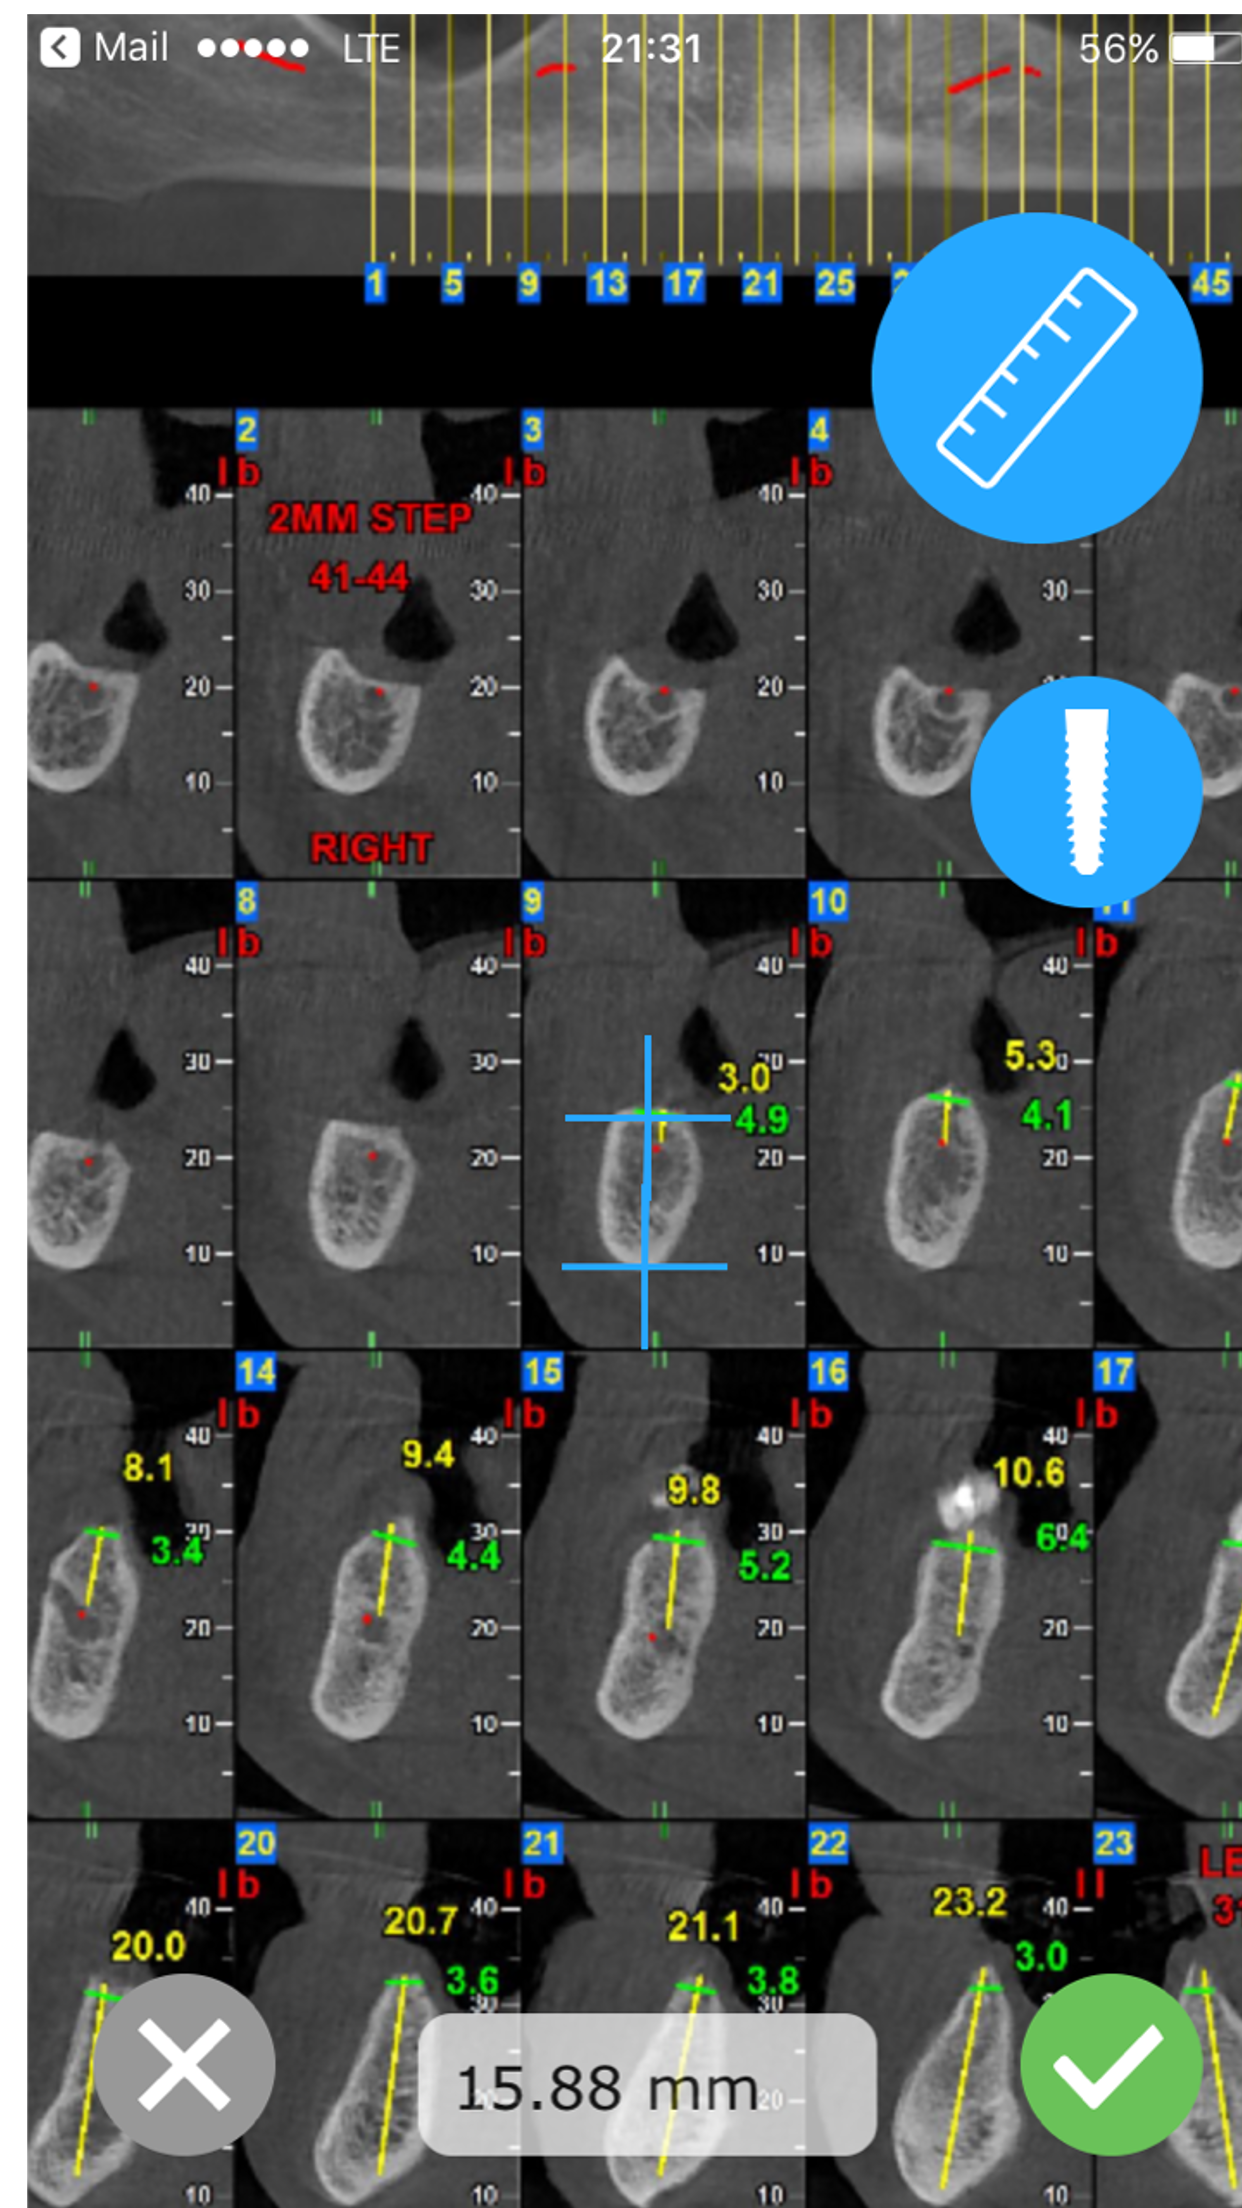

CBCT-Ruler was developed by Maxillofacial surgeon, to make the process of pre-surgical planning easy and mobile. The app opens a CBCT PDF file send by Dental imaging center and helps the practitioner easily measure distances. Another feature for the implant specialist, allows to introduce an implant to the CBCT, move the implant and align it. Check www.cbctruler.com for more information